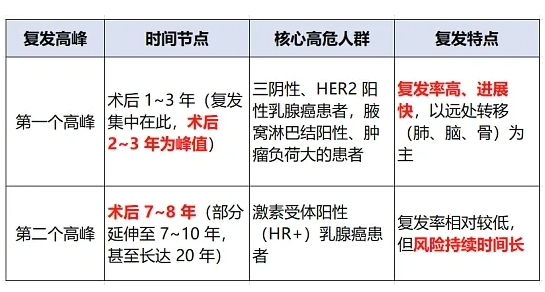

乳腺癌:分型不同,复发规律不一样

乳腺癌整体预后不错,但不等于不会复发。三阴性乳腺癌、没做靶向治疗的 HER2 阳性乳腺癌,术后 1 到 3 年是复发高峰;激素受体阳性的乳腺癌,前几年风险低,但术后 5 到 7 年甚至 10 年后,依然有复发可能。

术后该吃内分泌药的,一定要坚持吃,别自己随便停药。定期做乳腺超声、钼靶,要是出现骨痛、咳嗽、头痛,别大意,及时排查是不是转移。